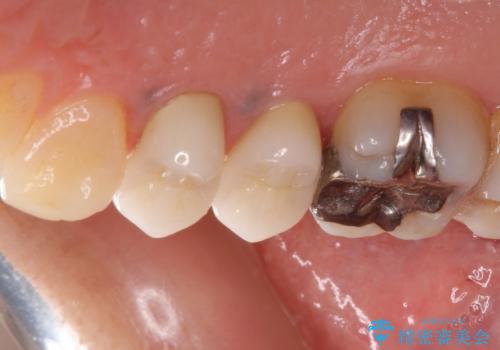

- クラウンが割れて治療を行っていたものの、途中で放置してしまったとのことで来院された患者様です。

根管治療を行った後に、ガラス系セラミッククラウンにて補綴することとしました。